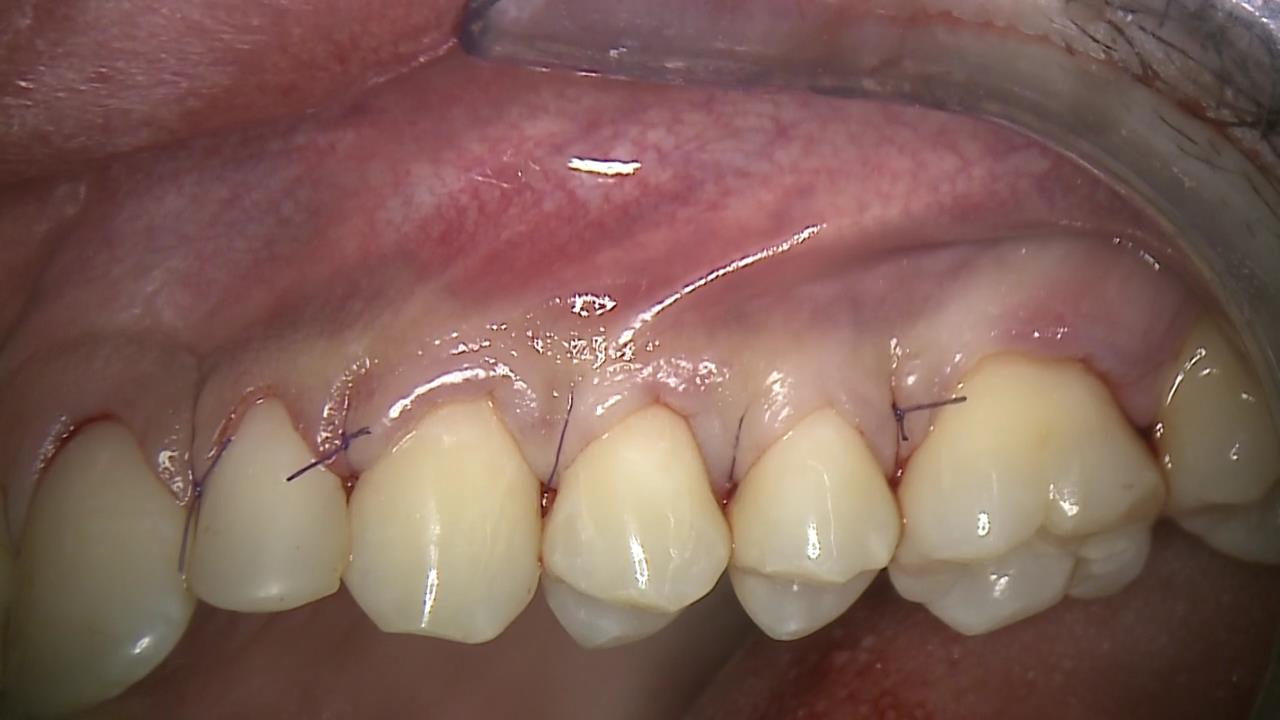

10/12 - Coronally advanced flap closure: note that the matrix is completely covered by the flapMultiple recession coverage with mucoderm® and Straumann® Emdogain® - 4 year follow-up - Prof. G. Zucchelli & Dr. M. Stefanini